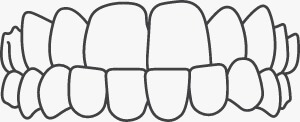

An open bite is where the front teeth do not overlap the lower teeth. This is caused by oral habits like finger sucking, tongue thrusting, or when the jaws don't grow evenly.

When one or more upper teeth bite on the inside of the lower teeth, this condition is called a crossbite. This can happen on either one or both sides of the jaw and affect front or back teeth.

Normally, there should be overlap of 2 mm but when the upper front teeth overlap the lower front teeth for more than 2mm such that they do not touch at all; an overbite is seen.

This occurs when there are gaps between the teeth and is the opposite of crowding. This can occur between two or more teeth and can be caused due to missing teeth, smaller teeth or oral habits like tongue thrusting, thumb sucking.

When teeth that are crooked and overlap mainly due to lack of space, this condition is called Crowding. Some of the causes include improper eruption of teeth, early or late loss of milk teeth or when teeth are larger than the space available in the jaw.

An underbite occurs when the lower teeth protrude past the front teeth, preventing normal function of your front teeth or molars.